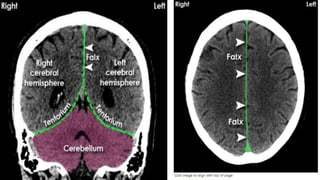

THE MENINGES

1. Using spin-echo sequences

2. The dura mater may be recognized as a short,

intermittent, thin, hyperintense, curvilinear structure on

contrast-enhanced T1-weighted MRI.

3. The pia mater and the arachnoid mater do NOT enhance

in normal subjects

• Flax